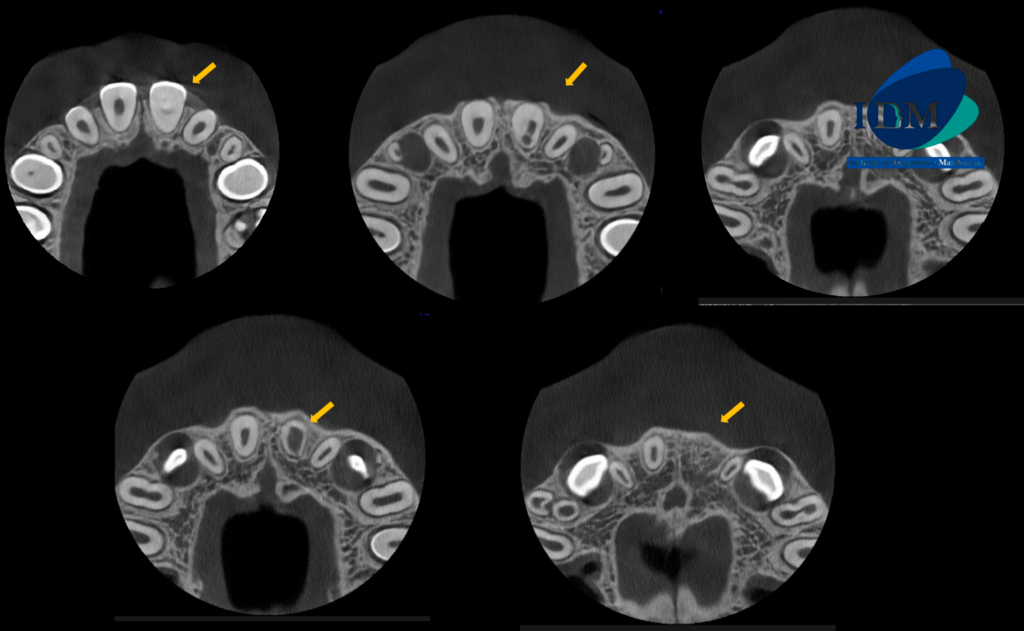

A la evaluación de la tomografía volumétrica (cone beam) de campo reducido en los cortes axiales (Figura 2) y transaxiales (Figura 3) se observa la pieza 21 con material restaurador coronal, obliteración de cámara y conducto radicular en tercio cervical y medio; además de observar la formación radicular incompleta caracterizado por tercio apical de conducto y foramen apical amplio; signos compatibles con secuela de trauma dental.

CORTES TRANSAXIALES